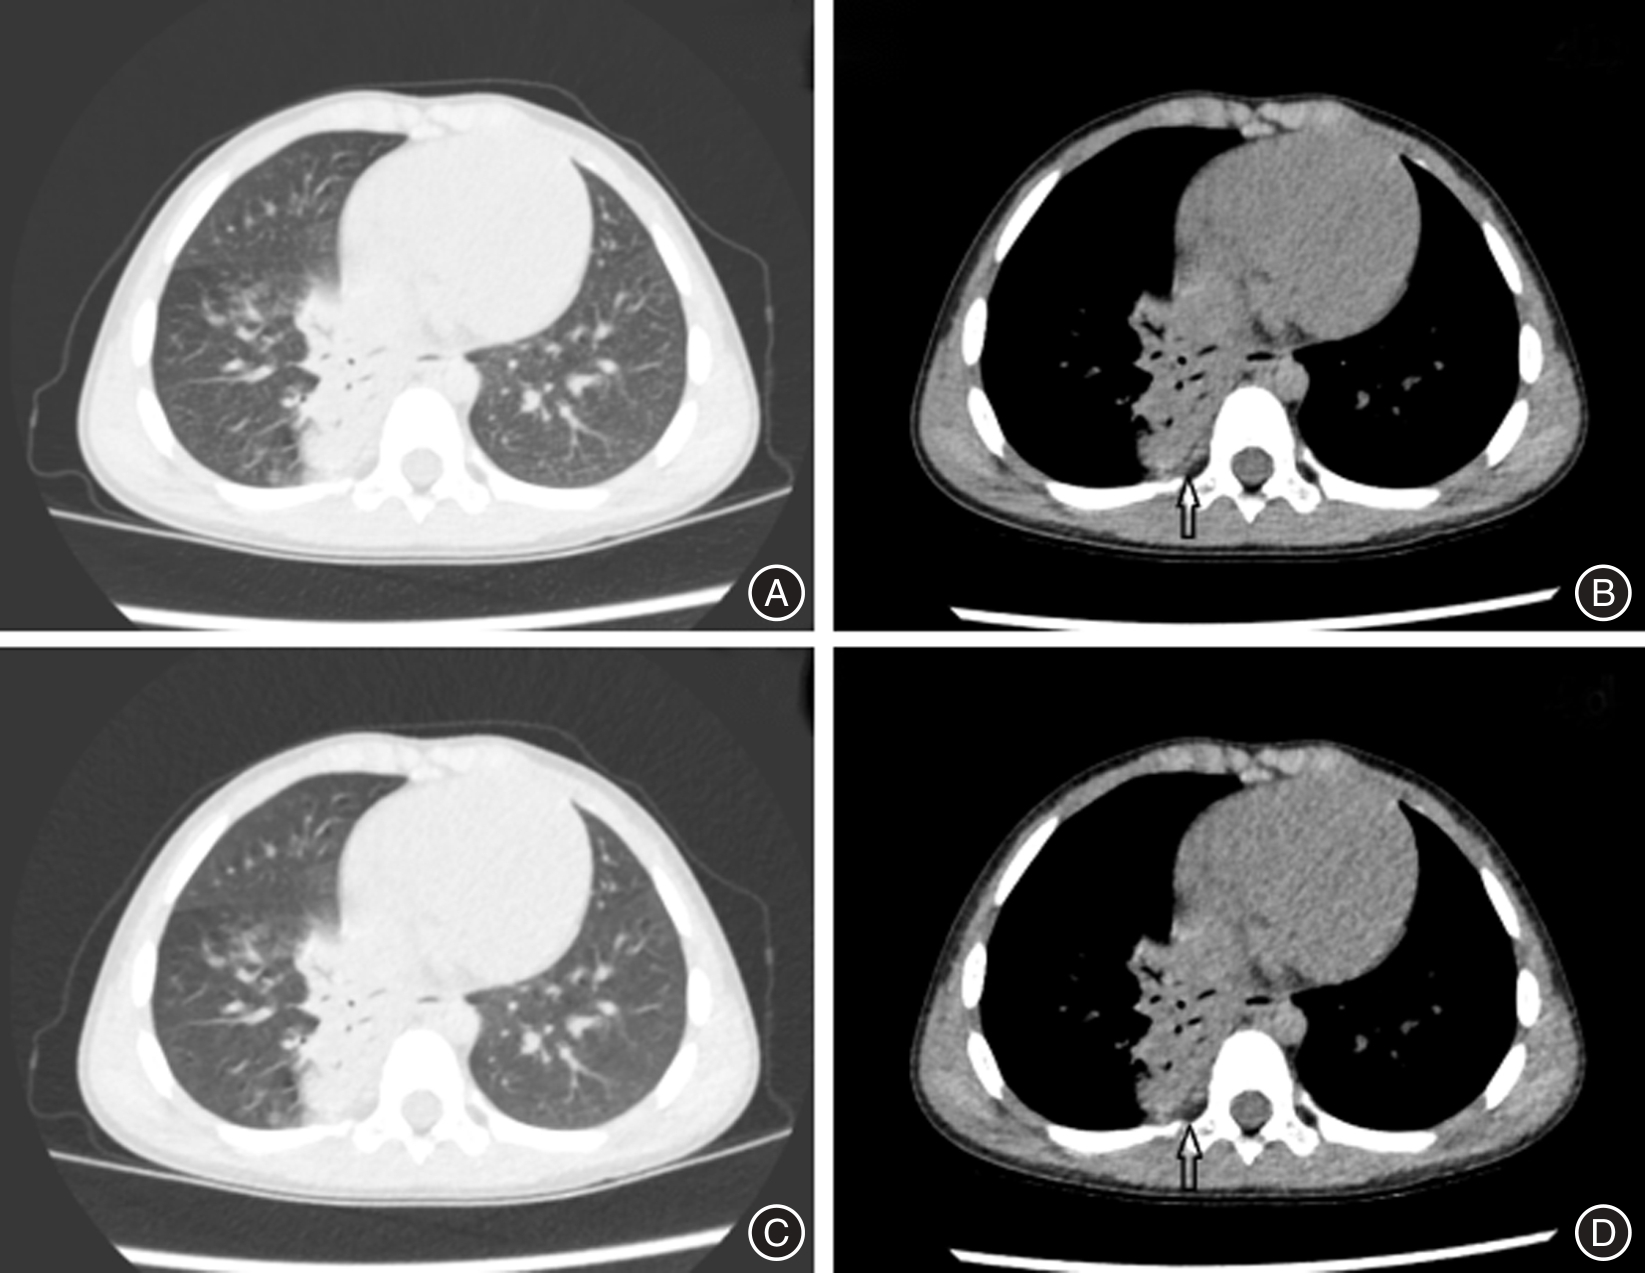

Tab.1

Comparison of objective image quality between DLIR and ASIR-V"

| 项目 | SD(HU) | SNR | CNR |

|---|---|---|---|

| ASIR-V20% | 33.75 ± 5.02 | 10.81 ± 2.40 | 12.06 ± 3.49 |

| ASIR-V50% | 26.40 ± 4.81 | 12.96 ± 2.72 | 16.44 ± 3.65 |

| ASIR-V80% | 19.77 ± 4.53 | 16.67 ± 3.58 | 23.70 ± 4.22 |

| F值 | 340.901 | 162.392 | 383.056 |

| P值 | < 0.001 | < 0.001 | < 0.001 |

| DLIR-L | 28.64 ± 4.04 | 12.11 ± 2.82 | 13.62 ± 3.74 |

| DLIR-M | 21.89 ± 3.50 | 16.45 ± 3.75 | 18.81 ± 3.92 |

| DLIR-H | 14.81 ± 4.15 | 20.95 ± 4.40 | 28.73 ± 4.31 |

| F值 | 501.301 | 226.671 | 590.284 |